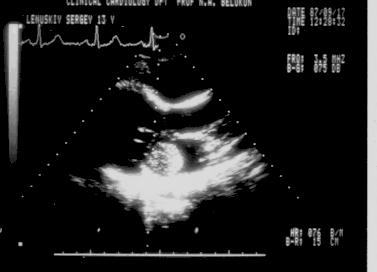

Миксома левого предсердия, пролабирующая в левый желудочек.

Рис.156

Миксома левого

предсердия,

пролабирующая

в левый желудочек.